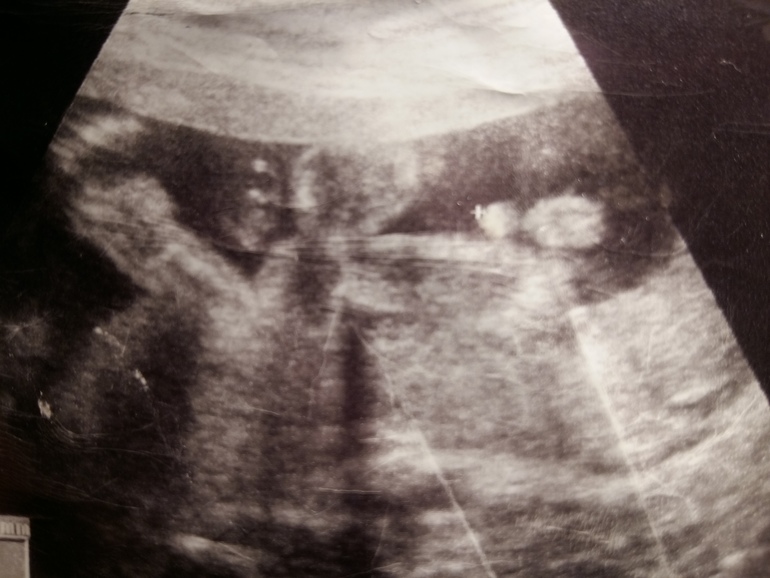

С первым на втором и третьем скринингах сказали мальчик, и не ошиблись. На третьем даже выдали фото причендал, фото похоже как у девушки ниже.

У меня у обоих такие же "причиндалы" были, на 20-й неделе) А сейчас что-то виднеется между ножек, но не чётко)

Вот у нас в 20 недель все достоинства отлично видны у старшего)